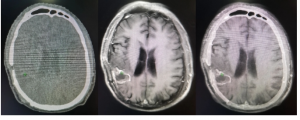

关爱老人 关注记忆——阿尔茨海默病 [2024-07-18]

关于阿尔茨海默病,其实一直流传着这样一句话:他们没有痴呆,他们只是回归孩子的状态!也有人说,阿尔茨海默病患者的脑海里像是有一块橡皮,会逐...